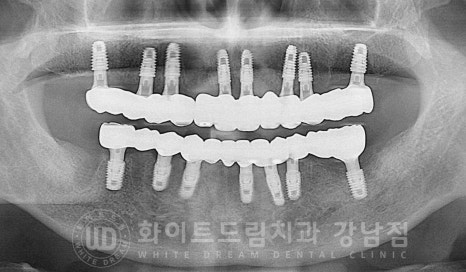

환자분의 수술 후 구내 사진입니다.

출혈이 조금 있어 흑백으로 처리를 했는데요.

대부분의 임플란트들은 잇몸뼈의 골 상태가 양호하여

2차 수술(임플란트를 겉으로 노출시키는 수술)까지 진행을 했고

앞서 안내드린 23번 임플란트 수술 부위만 1차 수술(잇몸뼈 안에 임플란트를 식립하는 수술)까지

진행을 하게 되었습니다.

내원 거리가 조금 머신 김포에서 내원을 하시는 분이셔서

최소한의 내원 횟수로 빠르게 치료를 받기를 원하셔서

총 2회의 수술로 나누어(상악 전체 식립, 하악 전체 식립) 전악 임플란트를 식립하기로

치료 계획을 세우게 되었습니다.

환자분의 치료 전/후 사진입니다.

[동일 인물이며 동일 환경에서 촬영되었습니다.]

기간 : 24.04.29 - 24.10.10

이렇게 잃어버린 전체 치아를 다시 완성하는데

수술 후 총 5회의 내원만 해주셨고

전체 임플란트 치료 기간도 6개월이 채 되지 않게 완료가 되었습니다.